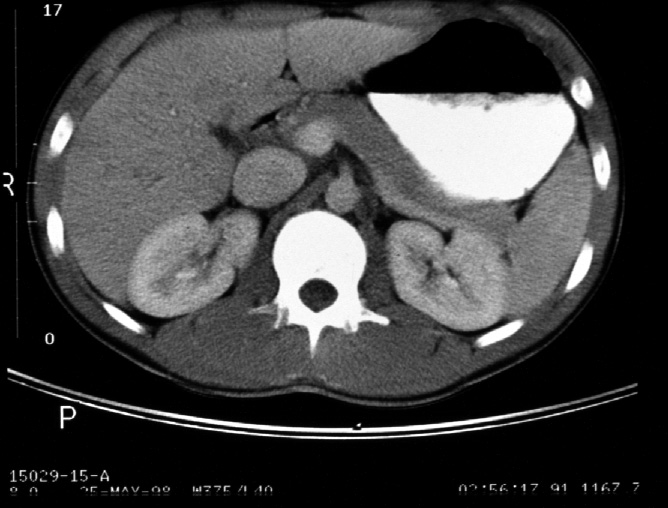

Identify -- stomach, liver, right kidney, left kidney, aorta, inferior

vena cava, diaphragmatic crura, portal vein, pancreas, splenic vein, spleen